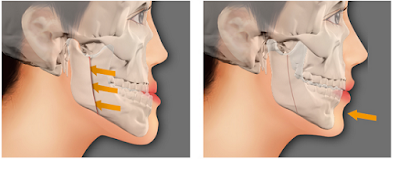

Móm do xương hàm

Có thể do hàm trên kém phát triển, hàm dưới phát triển quá mạnh, hoặc do dị tật khe hở vòm miệng làm xương hàm trên thiếu hụt kích thước khiến cho răng hàm trên luôn ở phía trong so với răng hàm dưới. Để điều trị móm do xương hàm cần phải phẫu thuật tạo hình, phương pháp này mang lại cho bạn một hàm răng đẹp chỉ sau một lần điều trị. Phẫu thuật móm được ưa chuộng trên thế giới, bởi bên cạnh yếu tố thẩm mỹ, nó còn đảm bảo về sự an toàn, không làm ảnh hưởng tới chức năng vùng răng, hàm, mặt.

Đối với trường hợp móm(vẩu) quá mức, các rối loạn khớp cắn và khớp thái dương hàm, làm mất cân xứng giữa xương hàm mặt và khối xương sọ thì niềng răng cũng khó khắc phục hết hoàn toàn, bác sỹ chỉnh nha kết hợp cùng với bác sỹ tạo hình.